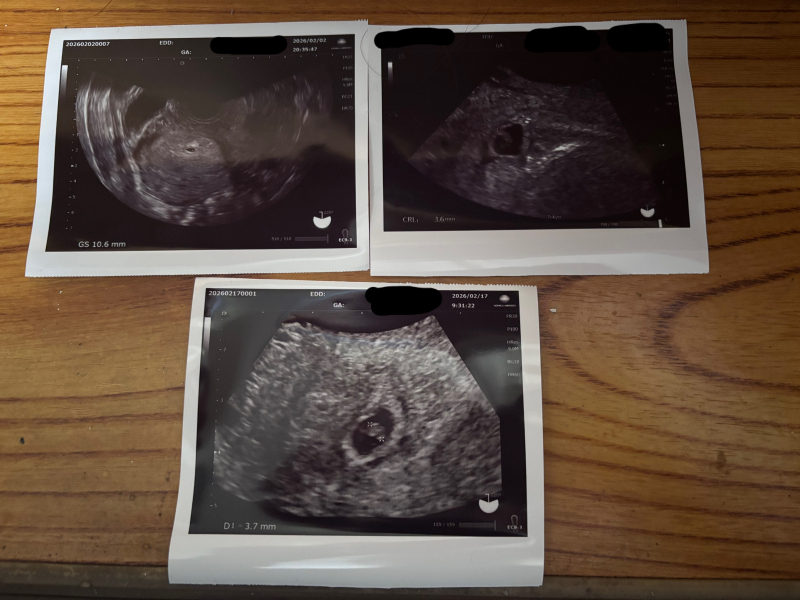

4週6日で胎嚢確認→6週4日で心拍確認

それが7週ちょうどでした。その時にエコーをしてもらったのですが、胎芽3.7mmと小さいと言われました。6週4日のエコーでは胎芽3.6mmでした。

7週に入った検診では、心拍も確認できていました。ですが、胎芽小さいと言われとても不安で心配です。上の子3人の時は平均くらいで何事もなく順調にいき無事に出産しました。